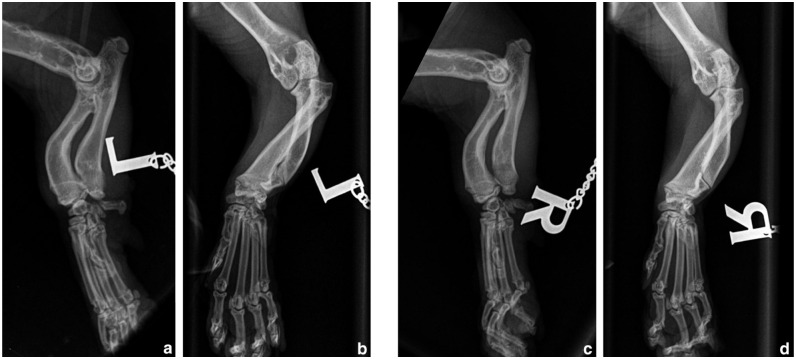

Case summary: A 10-month-old male neutered Dwelf cat with bilateral thoracic angular limb deformity secondary to chondrodystrophism presented with an acute onset of left thoracic lameness due to elbow subluxation and radial head displacement. Financial restrictions limited treatment to a single surgical procedure consisting of a left ulnar osteotomy, radioulnar polypropylene toggle placement and two temporary radioulnar transosseous K-wires. The lameness resolved but a degree of radial head subluxation persisted, radiographically similar in degree to the contralateral limb.